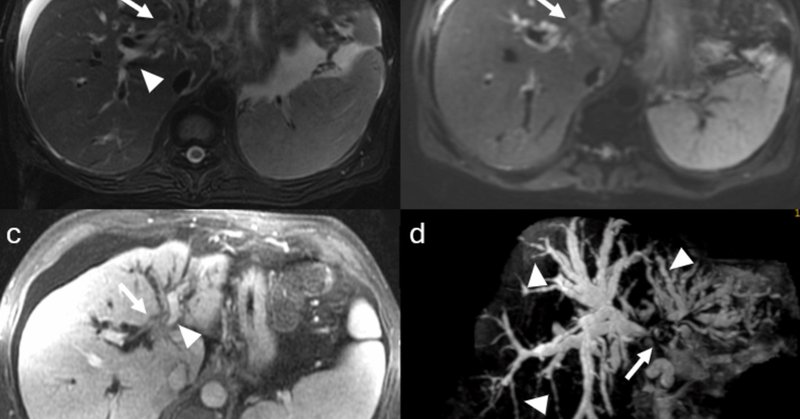

Axial diffusion weighted imaging: mass and filling defects demonstrate hyperintense signal on high B value diffusion imaging •MRCP and axial T2 fat saturation: diffuse intrahepatic biliary duct dilation; axial T2 fat saturation images confirm HASTE findings.

•Axial and coronal T2WI (HASTE sequences): An ~9cm hepatic mass with heterogenous, but predominately hyperintense signal, on T2WI. Associated intrahepatic biliary duct dilation with multiple curvilinear hypointense striations/filling defects.